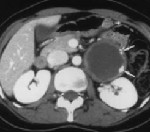

Диагноз устанавливается на основании жалоб, результатов внешнего осмотра и дополнительных исследований. Пациентов с подозрением на забрюшинную опухоль направляют на УЗИ, КТ и МРТ органов брюшной полости и забрюшинного пространства. Перечисленные диагностические методы позволяют определить структуру и локализацию новообразования, оценить степень вовлеченности близлежащих органов и выявить отдаленные метастазы в печени. Учитывая ряд признаков (форма, плотность, наличие или отсутствие капсулы, уровень гомогенности, степень васкуляризации), после проведения УЗИ, МРТ и КТ специалист может оценить злокачественность забрюшинной опухоли и выдвинуть обоснованные предположения о типе новообразования.